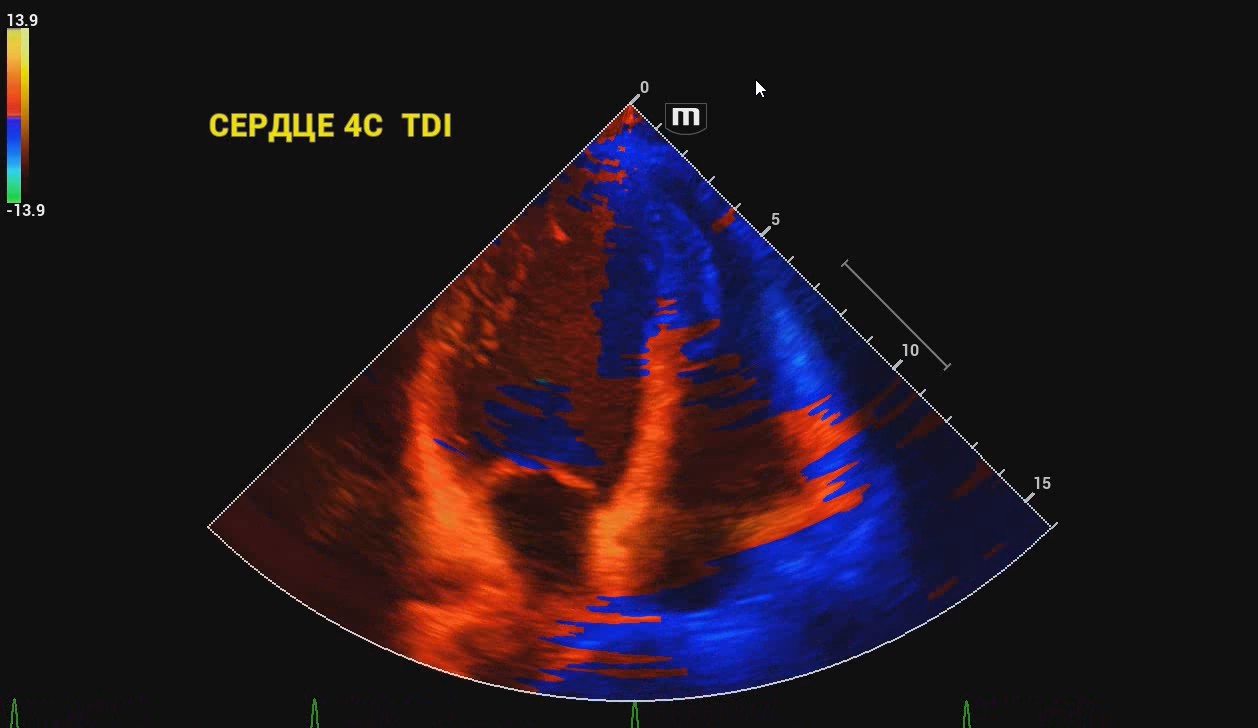

Платформа ZST+ Платформа ZST + — это уникальное инновационное решение, являющееся новой ступенью развития технологий в области ультразвуковой диагностики. В основе данной платформы - преобразование метода обработки ультразвуковых данных из традиционной в зонную, благодаря чему преодолевается традиционный компромисс между пространственным, временным разрешением и однородностью изображения ткани, что обеспечивает исключительное качество визуализации.